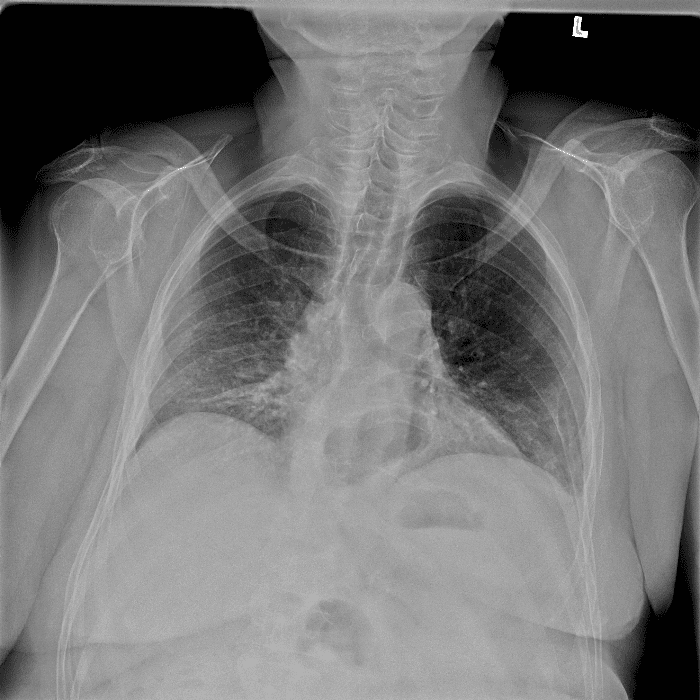

Practice Cases